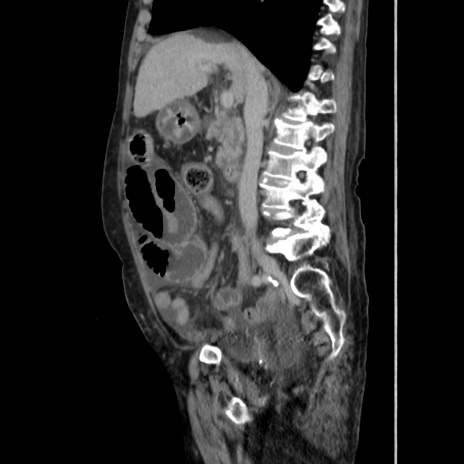

症例31(矢状断像)

【症例】80歳代 女性

【主訴】腹部膨満感

【現病歴】他院にて肝硬変にてフォロー中。1週間前から便秘、腹部膨満感、臍部腫瘤あり受診となる。

【既往歴】肝硬変

【身体所見】腹部膨隆あり、皮膚変化なし、疼痛なし。

【データ】WBC 4600、CRP 0.25